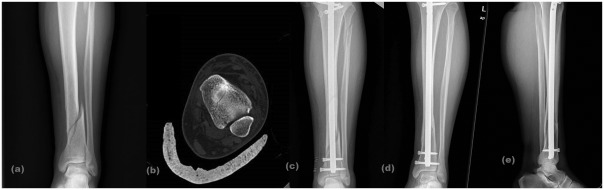

Fig. 2.

A 40-year-old female AO-OTA 43 C2 (a) preoperative X-ray, (b) preoperative computed tomography, c) early postoperative X-ray, (d, e) postoperative X-ray at 28th month.